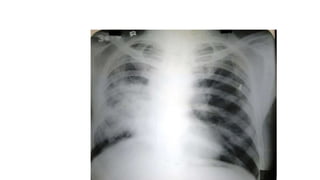

A normal chest x-ray shows the lungs, heart, bones, and soft tissues appearing healthy and unobstructed. The document discusses the different views used in chest x-rays, including PA, AP, lateral, and lateral decubitus views. It also covers topics like depth of inspiration, rotation exposure, the lobes of the lungs, identifying the heart, and how to read a normal chest x-ray.